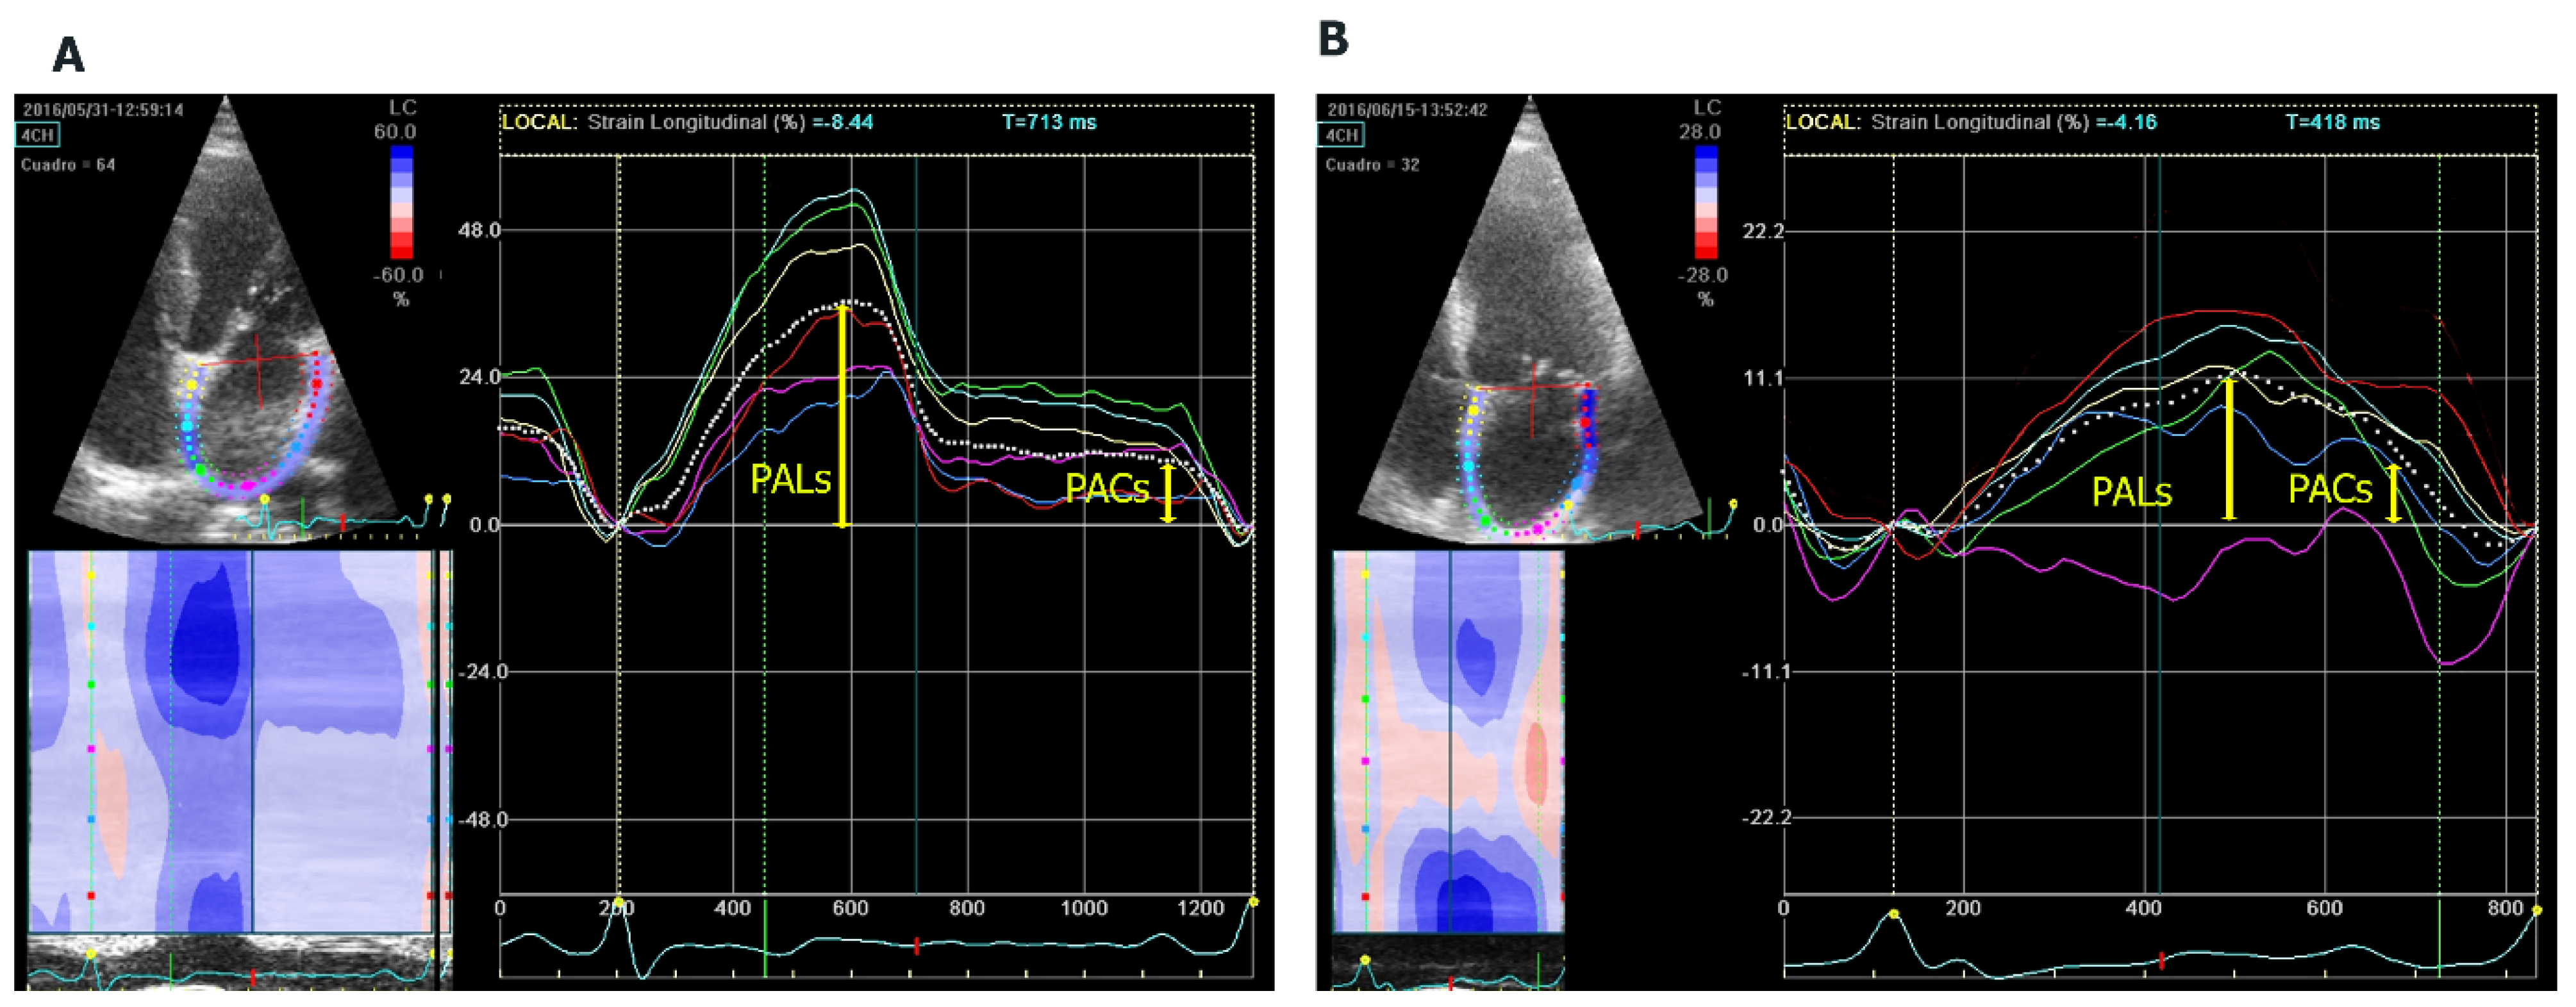

The atrial function study included left atrial ejection fraction (LAEF) and speckle tracking. For the analysis of biplanar LAEF, we used the following formula: maximum volume − minimum volume/maximum volume × 100. GE Q-analysis application was used to analyse the strain. Speckle tracking echocardiography is a technique that uses acoustic back-scatter (speckles) generated by the reflected ultrasound beam. The displacement of this speckles is considered to follow myocardial movement and represents myocardial deformation. LA endocardial surface is manually traced by a point-and-click approach in four-chamber view, between the mitral annulus to the opposite mitral annulus side and excluding pulmonary veins and LA appendage. An epicardial surface tracing is then automatically generated by the system, thus creating a region of interest (ROI), and after manual adjustment of ROI, width the software divides into six segments. Lastly, the software analyses and generates longitudinal strain curves for each segment and a mean curve of all segments. The speckle analysis reflects the pathophysiology of the left atrium: the maximum systolic global longitudinal strain (PALs), corresponding to the atrial reservoir phase, and the atrial contraction strain (PACs), corresponding to the contractile pump phase [17] (Figure 1). The frame rate was maintained at a level > 50 frames/s, and onset of the QRS complex was used as a reference point (R-R gating).

Figure 1.

Analysis of left atrial myocardial deformation by 2D speckle tracking. (A) Four-chamber (4CH) apical longitudinal strain of a patient without AF with normal strain and (B) a patient with AF and reduced strain. PALs: peak atrial longitudinal strain. PACs: peak atrial contraction strain.